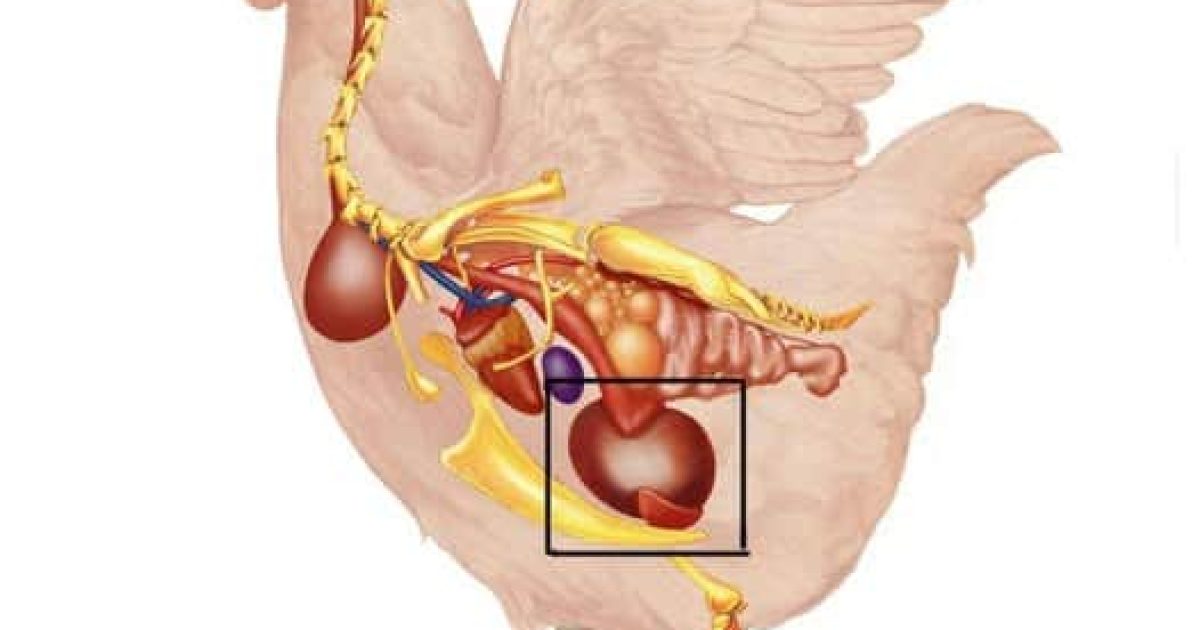

Mycoses : misez sur la prévention naturelle

Ongles qui changent de couleur, s’épaississent ou prennent des teintes jaunâtres ? Démangeaisons entre les orteils ? Le vinaigre de cidre aide à restaurer l’équilibre naturel de votre flore cutanée. Ses propriétés assainissantes freinent le développement des champignons, tout en protégeant la santé de votre peau. Bonus intéressant : utilisé régulièrement en bain de pieds, il représente une excellente mesure préventive.